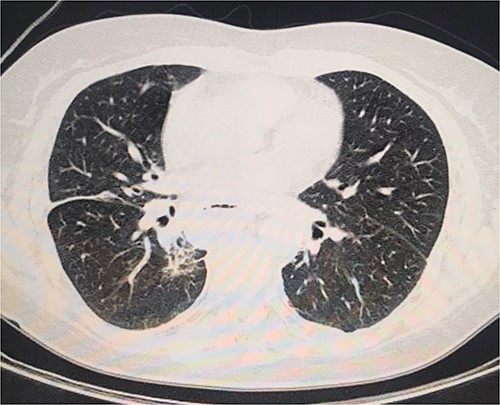

The abdominal computed tomography (CT) scan exhibited signs of esophagectomy with gastric lifting, a type IV hiatal hernia and colon herniation into the thorax (Fig. 1a and b). This was full of feces and symptoms of volvulus in the involved segment, with no free liquid in the cavity. Laboratory testing revealed an elevated protein C-reactive of 77, with normal white blood cells. Renal function and electrolytes were within normal limits.

Different sections of the CT study demonstrate the mediastinal position of the transversal volvulus. (a) Axial CT section of the abdomen showing signs of esophagectomy with gastric lifting, a type IV hiatal hernia and colon herniation into the thorax. (b) The coronal CT section of colon herniation into the thorax. (c) The sagittal CT section of the thorax and the abdomen shows the posterior mediastinal position of the colon herniation into the thorax.